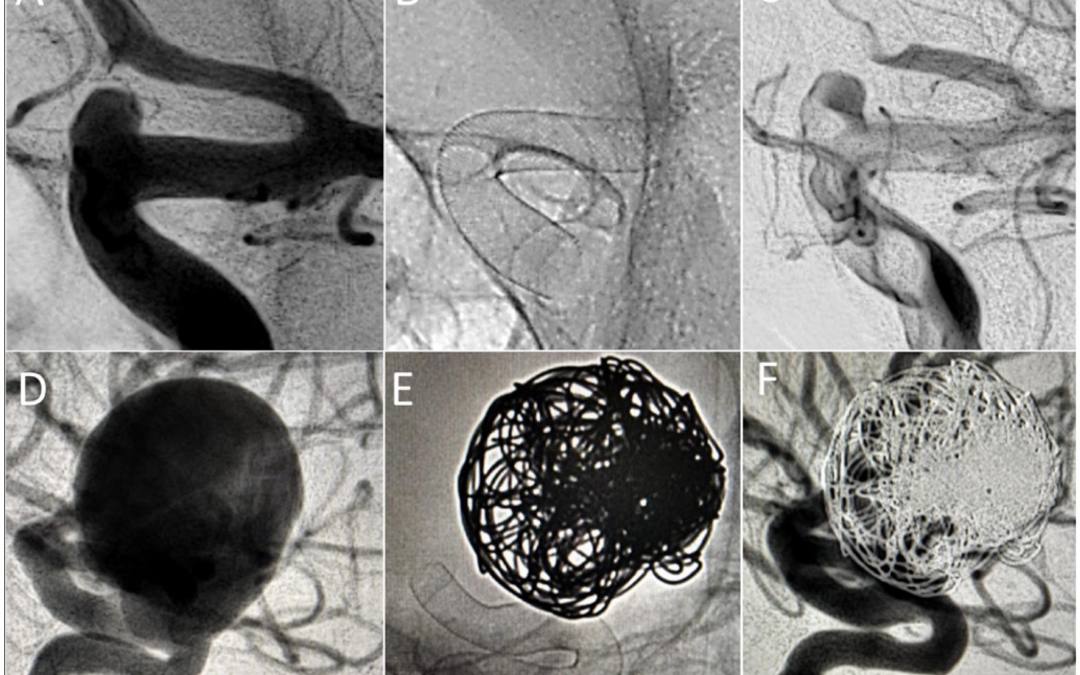

Primera experiencia multicentro con el derivador de flujo Silk Vista en 60 aneurismas intracraneales consecutivos: aspectos técnicos